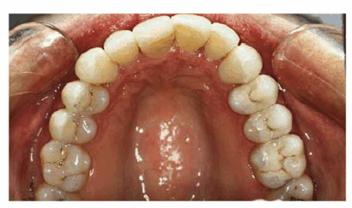

PROBLEM: This 38-year-old store owner presented with crowded and

discolored maxillary and mandibular teeth (Figures 24-7A, and 24-7B). Although orthodontic treatment was suggested as ideal

treatment, he elected a compromise that consisted of bonding the mandibular and

crowning the maxillary teeth.

Figure 24-7A: This 38-year-old man wanted to improve his crowded maxillary and mandibular teeth.

Figure 24-7B: This occlusal view shows why full orthodontic treatment was originally presented as the ideal treatment. The patient insisted on a "quick fix" solution.